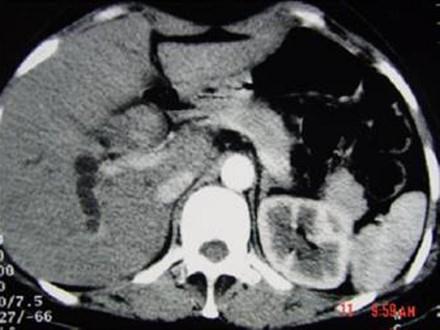

问题 女,35岁,右上腹痛一月,黄疸进行性加重,AFP阴性,消瘦乏力,影像检查如图,最可能的诊断为 ( )

选项 A、原发性肝癌 B、肝血管瘤 C、胆管癌 D、局灶性脂肪肝 E、肝转移癌

答案 C